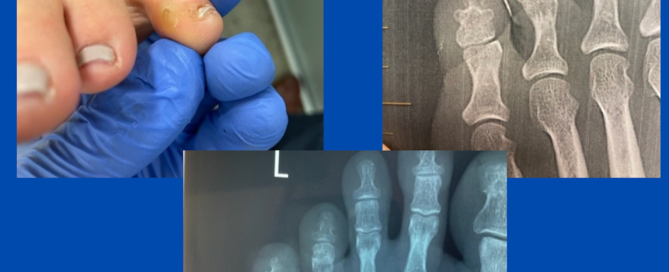

Ankylosed DIPJ and interdigital corn

Blog's main page This patient, who was referred to me for an opinion, had a markedly painful corn on the medial 5th toe that was becoming more symptomatic. On the [...]